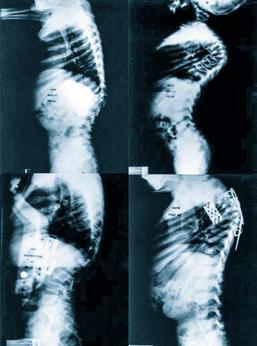

En 1976, el Dr. Eduardo Luque Rebollar presentó su técnica para la corrección de la escoliosis, que consistía en la desrotación segmentaria de las vértebras mediante la fijación de alambres sublaminares sujetos a dos barras paralelas colocadas a los lados de las

La técnica de desrotación vertebral “Luque”, se implementó en el Instituto Nacional de Ortopedia de forma alterna con otros procedimientos de estabilización quirúrgica previamente mencionados.

El consenso mundial de expertos en cirugía de columna reconoce que la etapa moderna de la cirugía se inicia con el uso de los nuevos elementos para estabilizar la estructura vertebral. Como mencioné anteriormente, en la Clínica de Columna iniciamos aplicando técnicas que estaban probadas para la escoliosis. Utilizamos halos cefálicos para tracción cervical, lo que nos permite lograr la reducción temprana de luxaciones cervicales; también empleamos

halos chalecos y la tenaza de Gardner Wells, que no habían sido aplicados en México para el tratamiento de trauma, como instrumentos de reducción.

Para la estabilización quirúrgica, inicialmente utilizamos las barras de “Harrington” de distracción y compresión, posteriormente utilizamos el sistema de “Luque” que modificamos para obtener mejor estabilidad en la reducción de fracturas, con muy buenos resultados. Con el desarrollo exitoso del sistema de “Cotrel-Dubousset”, mediante tornillos transpediculares, técnica que nos mostró y dirigió en su aplicación el Dr. Harry L. Shufflebarger, del Miami Children´s Hospital, iniciamos la exploración de otros sistemas similares como el TSRH del grupo médico del Texas Scottish Rite Hospital.

Una vez que iniciamos el uso de la técnica del Dr. Eduardo Luque R. para la estabilización vertebral, encontramos que la técnica presentaba un problema. Al ajustar los alambres sublaminares a las barras laterales, se desplazaban hacia la línea media, perdiendo estabilidad y facilitando la rotación. Además, las barras rectas forzaban las curvaturas vertebrales naturales, originando “espaldas planas”. Esto se solucionó al diseñar una barra en forma de rectángulo, cerrando los extremos firmemente con un codo, lo que nos permitía modelarla sobre las curvaturas de la región vertebral, mejorando la estabilidad sin deformar el perfil del raquis. Esta técnica sigue siendo utilizada en la actualidad, para algunos pacientes. Resultados publicados.